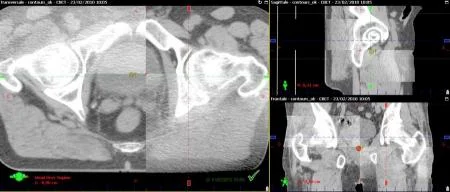

• Tomografía computarizada y Resonancia magnética

Tomografía computarizada y Resonancia magnética

Desarrollo de la tomografía computarizada (TC) y la resonancia magnética (RM), que permiten una mejor visualización de los tumores y los tejidos circundantes, lo que lleva a una planificación de tratamiento más precisa.